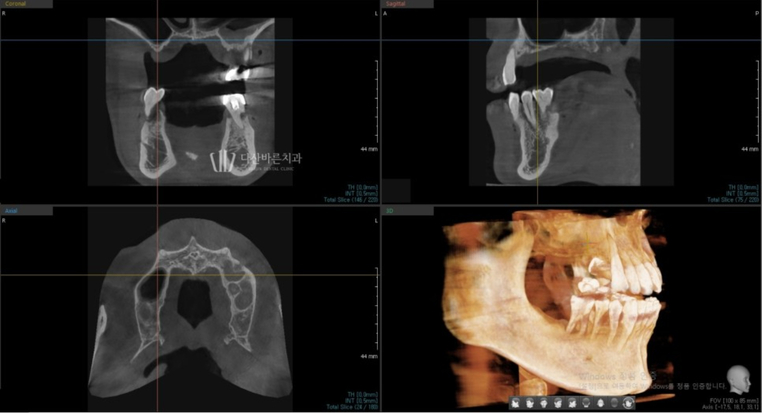

CT 3D cắt lớp (Nguồn: 3di)

Trên đây là ảnh chụp CT 3D cắt lớp giúp phân tích tình trạng xương nướu của bệnh nhân,

vị trí dây thần kinh,… và chuyển thành dữ liệu.

cấy ghép implant nhưng đã chụp CT 3D để chẩn đoán chính xác hơn độ dày và mật độ xương.

Vì răng đã mất lâu ngày và xương hàm bị mất nhiều

nên cần phải trồng răng implant ghép xương.

Sau khi ghép xương, vị trí và góc đặt implant được lên kế hoạch thông qua quy trình mô phỏng.

Ảnh trên là ảnh chụp quá trình cấy ghép implant mô phỏng.

Với bức ảnh này, bạn có thể kiểm tra trước độ dày của xương

có đủ hay không khi trụ implant (vít, vật cố định) nằm bên trong xương nướu,

sau đó đặt trụ implant ở vị trí và góc chính xác hơn.